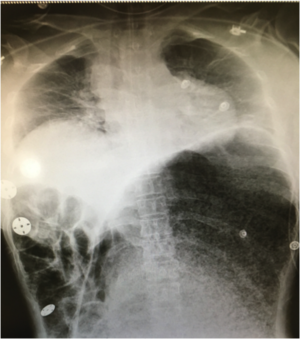

- Upright chest x-ray and abdominal series to assess for free air

- Can identify large distended stomach on x-ray